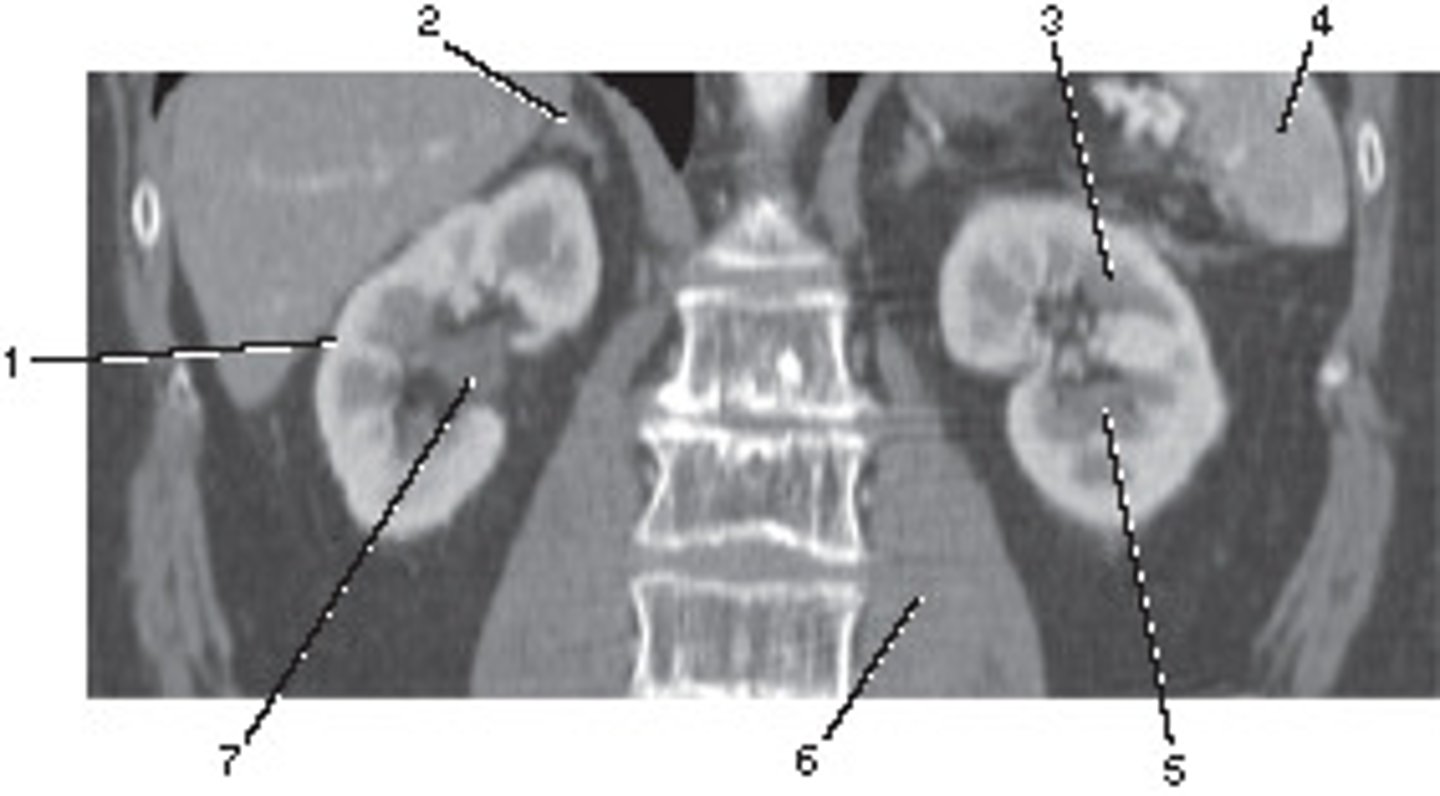

Corticomedullary;

30-40 seconds after injection,

the corticomedullary phase demonstrates optimal enhancement of the renal cortex with maximum differentiation from the renal medulla

This image of the abdomen was most likely acquired in which in which renal enhancement phase?

<p>This image of the abdomen was most likely acquired in which in which renal enhancement phase?</p>

Renal Cortex

Number 1 corresponds to which of the following?

<p>Number 1 corresponds to which of the following?</p>

45

Superior Mesenteric Artery

61